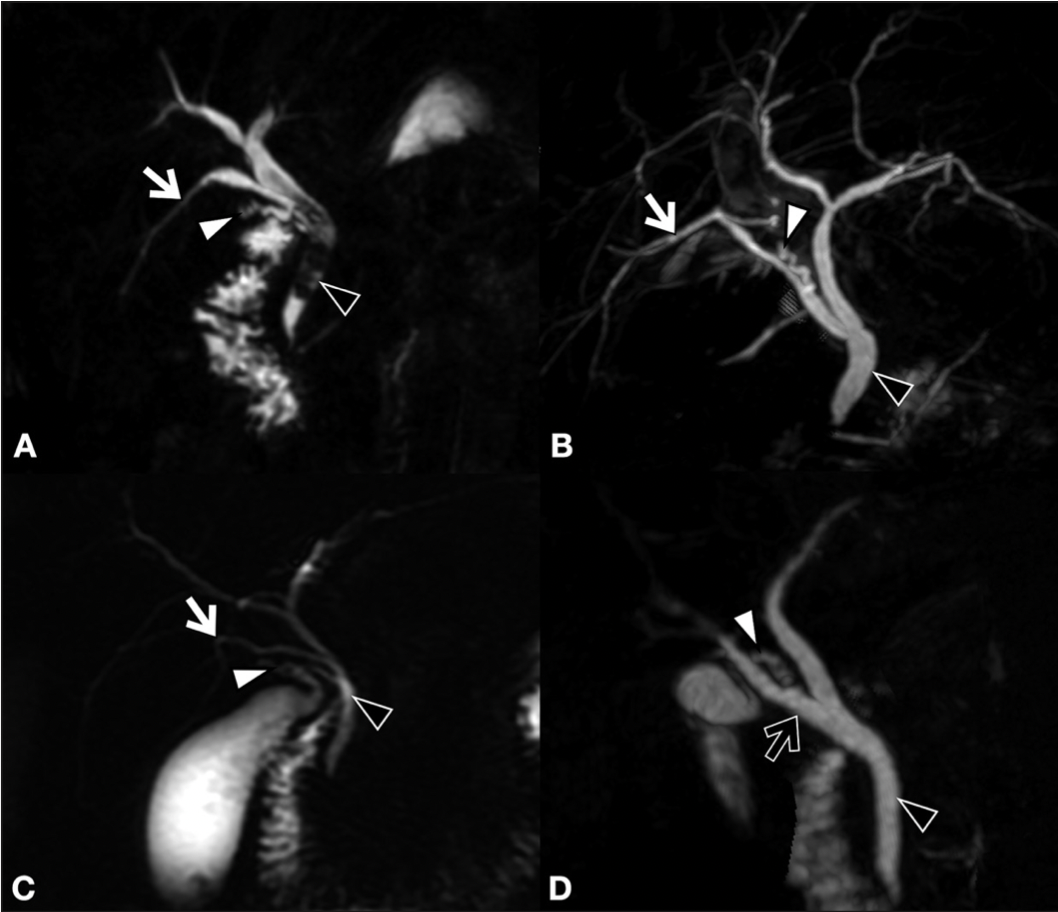

La finalidad de esta revisión es mostrar el estado actual de las lesiones de vía biliar (LVB), producidas especialmente durante la colecistectomía laparoscópica. Revisaremos la etiopatogenia, los grados de compromiso biliar, las lesiones vasculares asociadas, las clasificaciones utilizadas y los factores de riesgo. Además la forma como evaluar oportunamente la magnitud de la lesión, tanto en la misma cirugía como en el postoperatorio. Igualmente se muestran las diversas alternativas terapéuticas empleadas. Todo con la finalidad de evitar graves complicaciones.